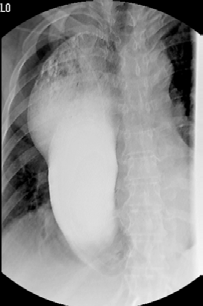

We report the case of a 63 year old woman with a history of type II diabetes mellitus and hypertension who had a squamous cell carcinoma (T2N0M0) in the middle third of the esophagus. According to the multidisciplinary team, the patient was operated onwithminimally invasive esophagectomy (thoracoscopy, laparoscopy and cervical esophagogastric anastomosis). During the first postoperative days no complications such as bleeding or infection were found. On the 7th postoperative day, oral contrast was given and there wasn´t any anastomotic leak. After starting with the progressive feeding, the patient went home on the 14th postoperative day. However, 5 days later, the patient came back to the hospital with the symptoms of postprandial fullness and vomiting. The esophagogastric study, CT and endoscopy showed a functional gastric tube stenosis secondary to rotation of the gastric tube. (Figures 1, 2 and 3). The stenosis itself was very elastic and the endoscope was passed-through easily.

few cases in the literature that use a stent to The first option we chose was the endoscopic dilation, butafter 3 attempts, it was not effective and the patient continued with intolerance to food. The second option was to place an undercover metallic stent by interventional radiologists, under general anesthetic. Initially it was effective but after 3 days, the stent migrated cranially. Finally, a 135mm length biodegradable SX-ELLA stent esophageal HV BIOMED® (ELLACS, Hradec Kralove, Czech Republic) was placed from the second portion of the duodenum to the prestenotic side of the gastric tube. This stent was endoscopically fixed with clips at its proximal portion to prevent its proximal migration (Figures 4 and 5). After two days of having placed the biodegradable stent, the oral contrast study was done and it showed no stenosis in the gastric tube (Figure 6). The patient was discharged on the third day after placing the stent eating soft food. After 5 months of stenting, the patient is completely asymptomatic.